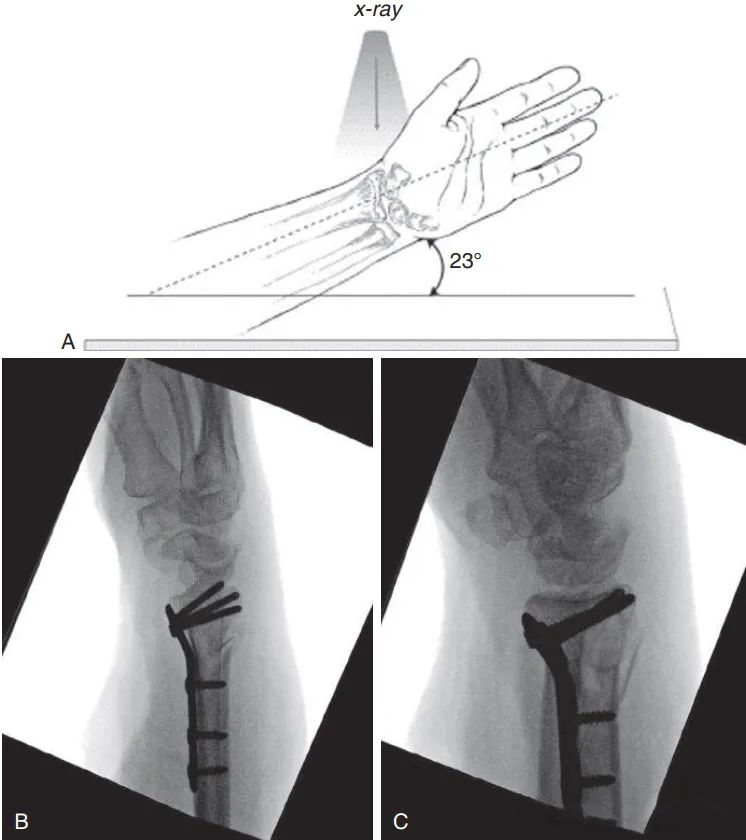

В настоящее время для оценки репозиции и положения винта используется внутренняя фиксация ладонной анатомической фиксирующей пластиной.Запястье приподнимается, чтобы компенсировать ладонный наклон и локтевую девиацию и избежать перекрытия суставных поверхностей: